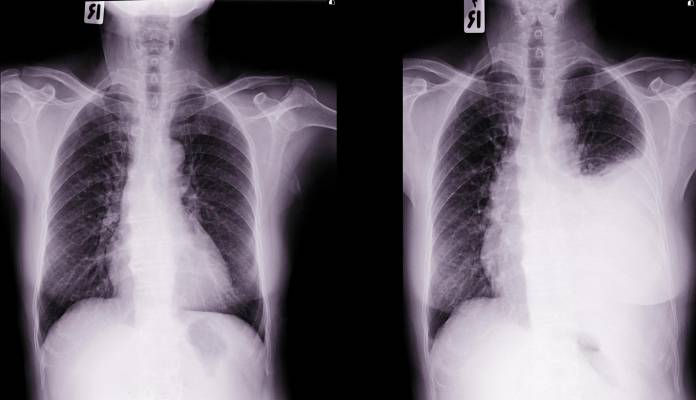

Im Patientengespräch erfragt der Arzt die Art der Beschwerden und die Dauer. In der klinischen Untersuchung wird er die Lunge abhören (Auskultation), bei einer Flüssigkeitansammlung ist das Atemgeräusch gedämpft. Außerdem wird er mittels Perkussion (Untersuchung durch Abklopfen der Körperoberfläche) auf einen gedämpften Klopfschall achten. Bei Verdacht auf einen Pleuraerguss kann dieser am einfachsten mittels Ultraschalluntersuchung nachgewiesen werden. Dies ist eine sehr sichere Methode, hier werden Flüssigkeitsansammlungen ab 10 bis 20 Milliliter erkannt. In Röntgenaufnahmen können Ergüsse über 250 Milliliter erkannt werden. Eine CT (Computertomographie) des Brustkorbs kann sehr kleine Flüssigkeitsmengen nachweisen.

Bei Verdacht auf einen Pleuraerguss werden bildgebende Verfahren angewendet, um das Vorhandensein von Flüssigkeit nachzuweisen. Ähnliche Beschwerden wie beim Pleuraerguss können folgende Erkrankungen verursachen: